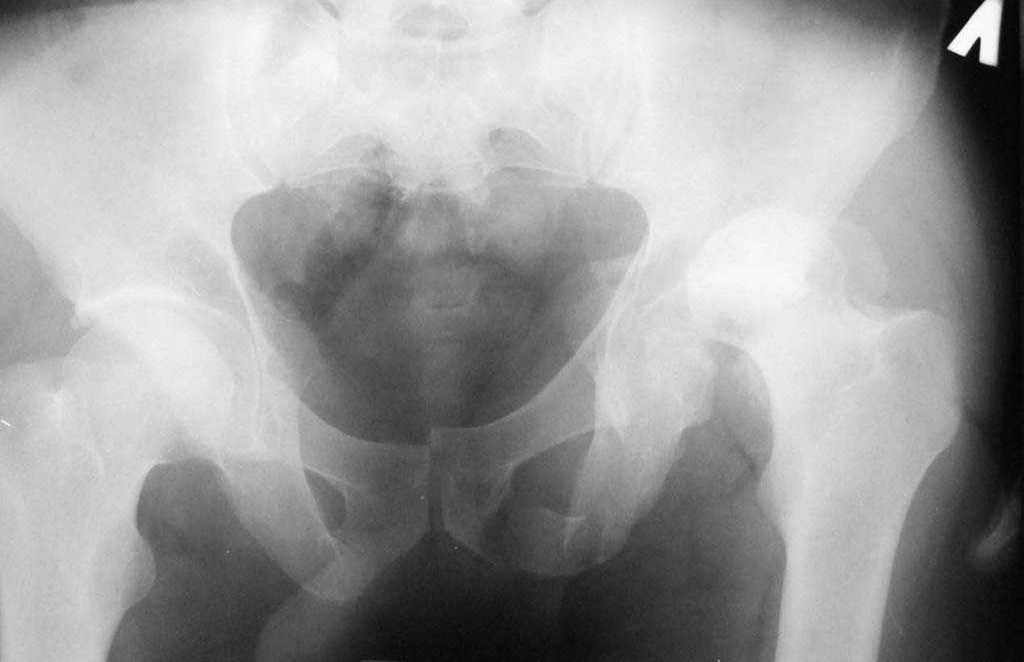

Re: перелом вертлужной впадины

Досылаю рентгенограмму